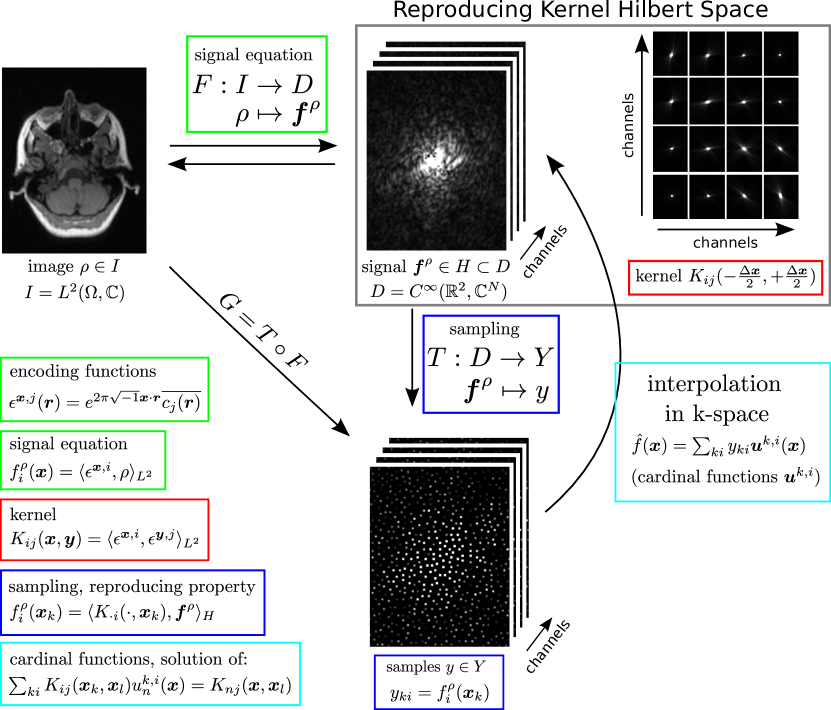

Refer to caption

Figure 1: Image reconstruction for parallel MRI as approximation in a reproducing kernel Hilbert space.

An overview of the theory developed in the following is shown in Figure 1. Please refer to Appendix 7.1 for some comments about the notation and to Table 1 for a list of important symbols.

We consider parallel imaging as an inverse problem with a linear forward model F:ID:𝐹𝐼𝐷F:I\rightarrow D, which maps from a Hilbert space of images I𝐼I to a data space D𝐷D. The range of F𝐹F is the space of ideal signals HD𝐻𝐷H\subset D. From the data space a set yY𝑦𝑌y\in Y of samples are acquired, which is described by a sampling operator T𝑇T. Then, the general setting is the following: